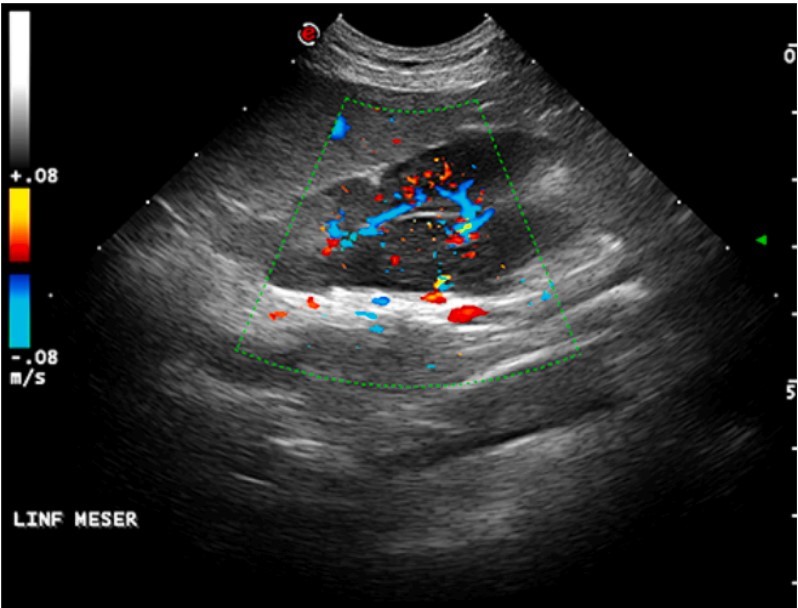

ارزیابی غدد فوق کلیوی به طور معمول در معاینه سونوگرافی شکم انجام می شود. به طور معمول غدد فوق کلیوی بسیار کوچک هستند، به شکل بادام زمینی سمت چپ، بیضیتر از سمت راست هستند. ارزیابی سونوگرافی غده فوق کلیوی راست ممکن است چالش برانگیز باشد، زیرا در مجاورت ورید اجوف دمی از نظر قدامی قرار دارد: وجود هوا در دستگاه گوارش یا معده پر از مایع/غذا شرایطی هستند که اغلب در ارزیابی آن اختلال ایجاد می کنند. اندازه، شکل، اکوتکسچر) غدد فوق کلیوی می تواند به تشخیص کمک کند. شایع ترین بیماری غدد فوق کلیوی شامل هورمون ترشح کننده یا غیر ترشح کننده است. سونوگرافی غدد لنفاوی اغلب در نواحی آناتومیکی مختلف انجام می شود و برای شکم نیز همینطور است. ارزیابی آنها ممکن است مشکوک به وجود بیماری بدخیم یا شرایط التهابی باشد. ویژگیهای سونوگرافی غدد لنفاوی مانند شکل، عروق، اکوژنیک به تشخیص بیماری در حال انجام کمک میکند (شکل 3).

شکل3. لنفوم در گربه نر 9 ساله خانگی. بزرگ شدن غدد لنفاوی شکمی هیپواکویک با منبع خون مخلوط ناف و محیطی.